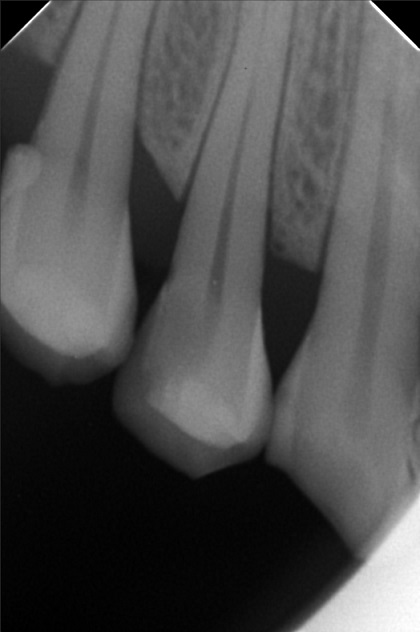

Edit Record Check our patient data records. Add patient information Patient Info Profile picture Last Name First Name Middle Name Birthdate Age Street Barangay City Country Zip Code Contact number Email Procedure 3/22/22- OP Lc 13 m/ 21 d/ 22 m/ 47 o/ b/ cervical xray 14 for rct 10/11/22 - OP (L); ACCESS #14, SCOUT #10 BL 18mm, EUGENOL. 10/14/22- 12/11/21/22- TF emax veneers 10/19/22 - 19mm, close w/ pulp devitalizer 09/02/23- op ** For change of crowns posterior Lower for Crown #15 08/13/24 OP 01/23/26 Alumina crwon #14 temporary crown OP Scanning File bangaros.jpg File 2 bongaros.jpg File 3 bongaros_02.jpg File 4 bongaros_03.jpg File 5 bongaros_04.jpg File 6 309497615_1081002115924778_349479569281481267_n.jpg File 7 bongaros_1.jpg File 8 bongaros_02_1.jpg File 9 File 10 File 11 File 12 File 13 File 14 File 15 File 16 File 17 File 18 File 19 File 20 Retain Record Retain Record Yes No Save Your Changes